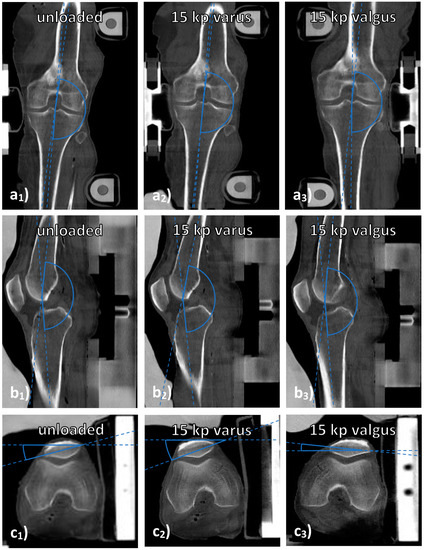

2.5.3. CT

CT datasets were analyzed to determine the joint’s alignment as a function of configuration. Because of the larger field of view, CT scans visualized the entire joint and loading device so that measures of joint alignment in the device could be taken on the respective CT scans. Joint alignment was quantified by determining the angles between the tibial and femoral shafts on sagittal (“joint extension” (popliteal angle)) and coronal reconstructions (“joint deviation” (lateral angle)) as well as between a line joining both corners of the patella and the horizontal line on axial reconstructions (“joint rotation”) (Figure 1). OS performed these measurements using the in-house PACS. Blinding proved impractical because each joint’s configuration was easily discernible.

Qualitatively, Figure 2 and Figure 3 indicate the loading-induced changes of the MFTC (Figure 2) and the LFTC (Figure 3) in a representative knee joint and in reference to respective histologic sections.

Joint alignment as assessed by CT was related to loading intensity and configuration (Table 6). As expected, joint deviation angles that were measured on the lateral side of the joint increased (or decreased) significantly under varus (or valgus) loading (p < 0.001), thereby indicating more varus and valgus morphotypes under loading. Joint extension angles decreased significantly under loading (p < 0.001), indicating steadily increasing joint flexion under loading, yet changes were more pronounced under varus than valgus loading. Joint rotation was significantly different, too, with external rotation observed under varus loading and internal rotation under valgus loading. Taken together, the joints tended to undergo moderate flexion and external rotation under varus loading as well as slight flexion and internal rotation under valgus loading.

Figure 1. Measurements of joint alignment on CT images. Visualized are coronal (a), sagittal (b), and axial (c) reconstructions of a representative knee joint under various loading conditions, i.e., unloaded (a1c1), under 15 kp varus loading (a2c2) and under 15 kp valgus loading (a3a3). “Joint deviation” was determined on mid-coronal images as the lateral angle between the femoral and tibial shafts (a). “Joint extension” was determined on mid-sagittal images as the popliteal angle between the femoral and tibial shafts (b). “Joint rotation” was determined on the axial images that demonstrated the largest diameter of the patella by relating the trans-patellar line (through the outer corners of the patella) to the horizontal line (c). By convention, external rotation was indicated by positive angles and internal rotation by negative angles.